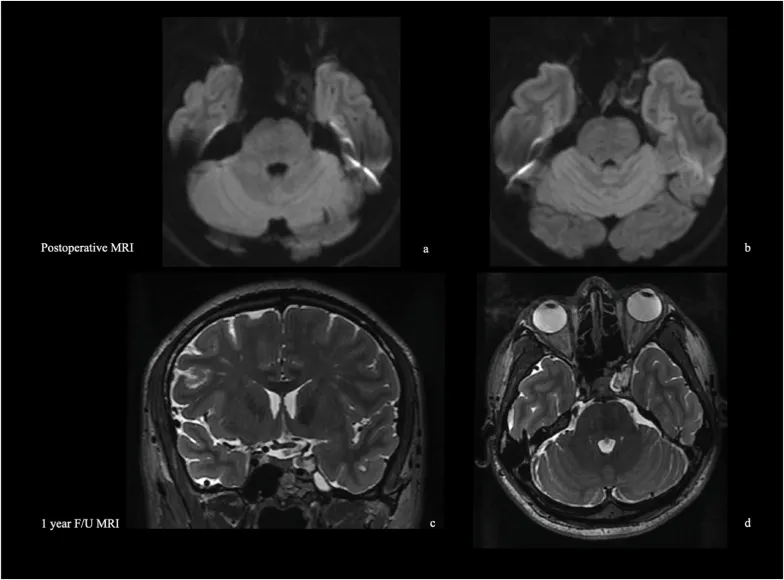

术后磁共振证实囊肿内容物完全切除(图7)。给予48小时抗生素预防,未观察到脑脊液漏。

图7:术后磁共振显示,海绵窦外侧壁上后内侧部分的囊肿已完全移除,囊壁被次全切除。术后即刻弥散加权磁共振影像显示,除对应于囊壁残余的微小局灶性信号外,无弥散受限表现。术后一年的随访中,冠状位和轴位T2加权磁共振影像显示海绵窦减压满意,其信号强度与脑脊液等信号,表明无复发迹象。

随访期间,上睑下垂完全消失,复视持续改善。

术后1年磁共振显示无复发,海绵窦减压满意,随访仍在进行中。